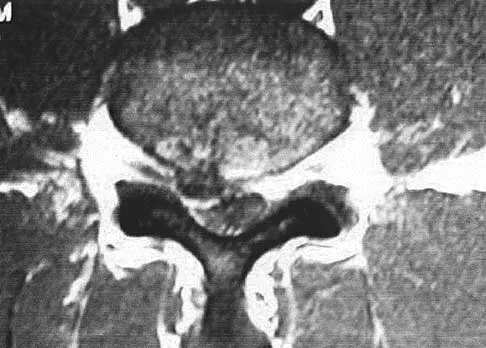

Figures 1a through 1c show the radiograph and MRI scans of a 16-year-old patient who has a painful hip. Examination reveals a significant limp, limited abduction and internal rotation, and severe pain with internal rotation and adduction. A biopsy specimen is shown in Figure 1d. What is the deposited pigment observed in this condition?

Explanation

Pigmented villonodular synovitis (PVNS) is a synovial proliferative disorder that remains a diagnostic difficulty. The most common clinical features are mechanical pain and limited joint motion. On radiographs, the classic finding is often a large lesion, associated with multiple lucencies. Other findings may include a normal radiographic appearance, loss of joint space, osteonecrosis of the femoral head, or acetabular protrusion. MRI is the imaging modality of choice and will show the characteristic findings of a joint effusion, synovial proliferation, and bulging of the hip. The synovial lining has a low signal on T1- and T2-weighted images, secondary to hemosiderin deposition. Copper deposition occurs in patients with Wilson's disease, which mainly affects the liver. Bhimani MA, Wenz JF, Frassica FJ: Pigmented villonodular synovitis: Keys to early diagnosis. Clin Orthop 2001;386:197-202.